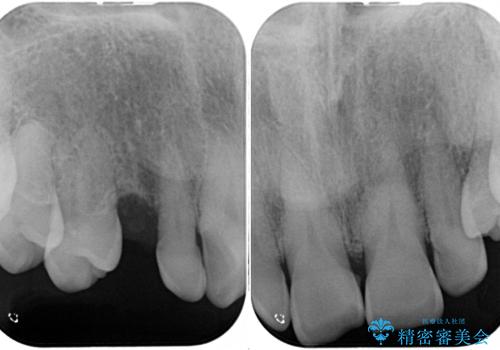

上顎の矮小歯は隙間が多く、歯軸の傾斜も大きかったため、部分矯正により補綴治療前に歯の位置を整えることとしました。

下顎の乳歯は支台歯として機能することは困難と思われたので、事前に抜歯をし、上顎の矯正治療終了のタイミングに合わせて、セラミックブリッジにて補綴治療することとしました。

前歯部はディープバイトという、上顎前歯が下顎前歯に深く覆い被さる咬合であったので、理想的には全顎矯正が必要となりますが、今回は患者希望により前歯部のみの部分矯正で対応しました。そのため下顎犬歯の神経を取り除くことになってしまったのは心残りであります。